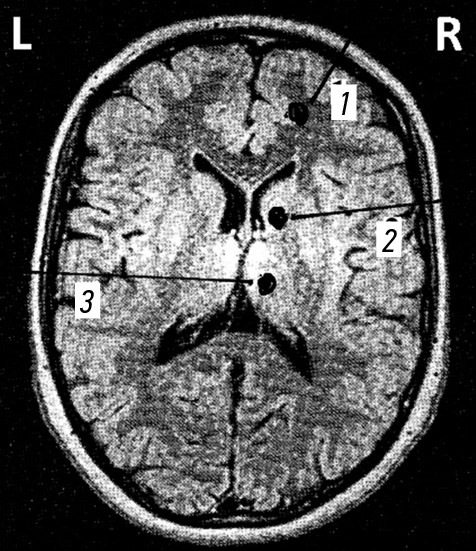

С опорой на данные табл. 4, структуры ГМ (по данным магнитно-резонансной томографии) были условно разделены на две анатомические зоны (рис. 1).

Рис. 1. Условное разделение головного мозга на зоны: a — сагиттальный срез; b — аксиальный срез. 1 — подкорковые образования, желудочки и ствол головного мозга; 2 — кора головного мозга и полушария мозжечка.

На основании тяжести огнестрельных ЧМР все ранения 2-й зоны также условно можно разделить на раневые каналы, проходящие ближе к конвекситальной поверхности ГМ, как более легкие, раневые каналы, проходящие ближе к 1-й зоне, как более тяжелые. К ним относят огнестрельные ранения мягких тканей, сопровождающиеся формированием контузионных очагов I и II вида и внутримозговых кровоизлияний, непроникающие ранения также с формированием контузионных очагов III и IV вида и внутричерепными гематомами и наружной желудочковой ликвореей. Среди проникающих ЧМР — это касательные проникающие ранения, простое слепое, сегментарное в пределах одной доли ГМ, рикошетирующие и передние парабазальные ранения в сочетании с повреждением лобных пазух и стенок орбиты. Все эти раненые после ПХО выжили и были переведены для дальнейшей реабилитации с различными очаговыми неврологическими нарушениями.

Все огнестрельные (пулевые и осколочные) ранения, раневой канал которых проходил через обе зоны, были наиболее тяжелыми. К ним относят проникающие огнестрельные ранения: диагональное, сегментарное двуполушарное (слепое, сквозное), радиальное одно- и двуполушарное, диаметральное и парабазальные ранения височно-сосцевидное, а также ранения задней черепной ямки. Среди этих раненых после ПХО часто наблюдали летальные исходы, у выживших — вегетативное состояние.